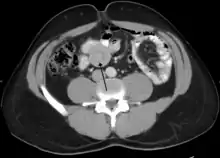

The cause in children is typically unknown; in adults a lead point is sometimes present.[1] Risk factors in children include certain infections, diseases like cystic fibrosis, and intestinal polyps.[1] Risk factors in adults include endometriosis, bowel adhesions, and intestinal tumors.[1] Diagnosis is often supported by medical imaging.[1] In children, ultrasound is preferred while in adults a CT scan is preferred.[1]

An intussusception is often suspected based on history and physical exam, including observation of Dance's sign. A digital rectal examination is particularly helpful in children, as part of the intussusceptum may be felt by the finger. A definite diagnosis often requires confirmation by diagnostic imaging modalities. Ultrasound is the imaging modality of choice for diagnosis and exclusion of intussusception, due to its high accuracy and lack of radiation. The appearance of target sign (also called "doughnut sign" on a sonograph, usually around 3 cm in diameter, confirms the diagnosis. The image seen on transverse sonography or computed tomography is that of a doughnut shape, created by the hyperechoic central core of bowel and mesentery surrounded by the hypoechoic outer edematous bowel.[11] In longitudinal imaging, intussusception resembles a sandwich.[11] It is also called "pseudokidney" sign because hyperechoic tubular centre is covered by a hypoechoic rim producing a kidney-like appearance.[12]